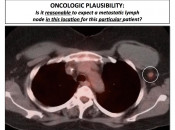

SUV’s must be interpreted in the context of the type of cancer and its specific presentation in the particular case at hand (“Oncologic Plausibility”).

We must ask ourselves whether this particular FDG-avid finding fits the clinical picture of malignancy (primary or metastatic) in this particular case?

If it does, we are almost always looking at malignancy, and should report it as such.

If, however, the finding does not fit a clinical picture, then we should be very cautious before reflexively reporting it as “suspicious for malignancy”. In these cases, we must first exhaust all other potential explanations for the finding. [Fig. 1]